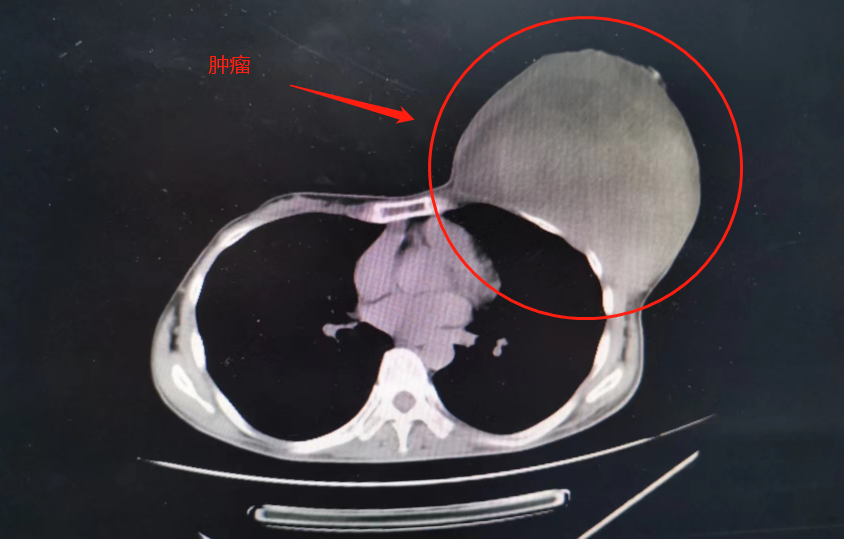

▲患者乳腺肿瘤

乳腺科杨伟雄主任在了解患者病情后,迅速组织多学科讨论,为患者制定了最优的治疗方案,术前输血后为患者实施完整的乳腺肿瘤切除术,并同时做了局部的皮瓣修复整形,让患者的乳房完美如初。切除的肿瘤大小约15*15cm,重量高达5公斤。